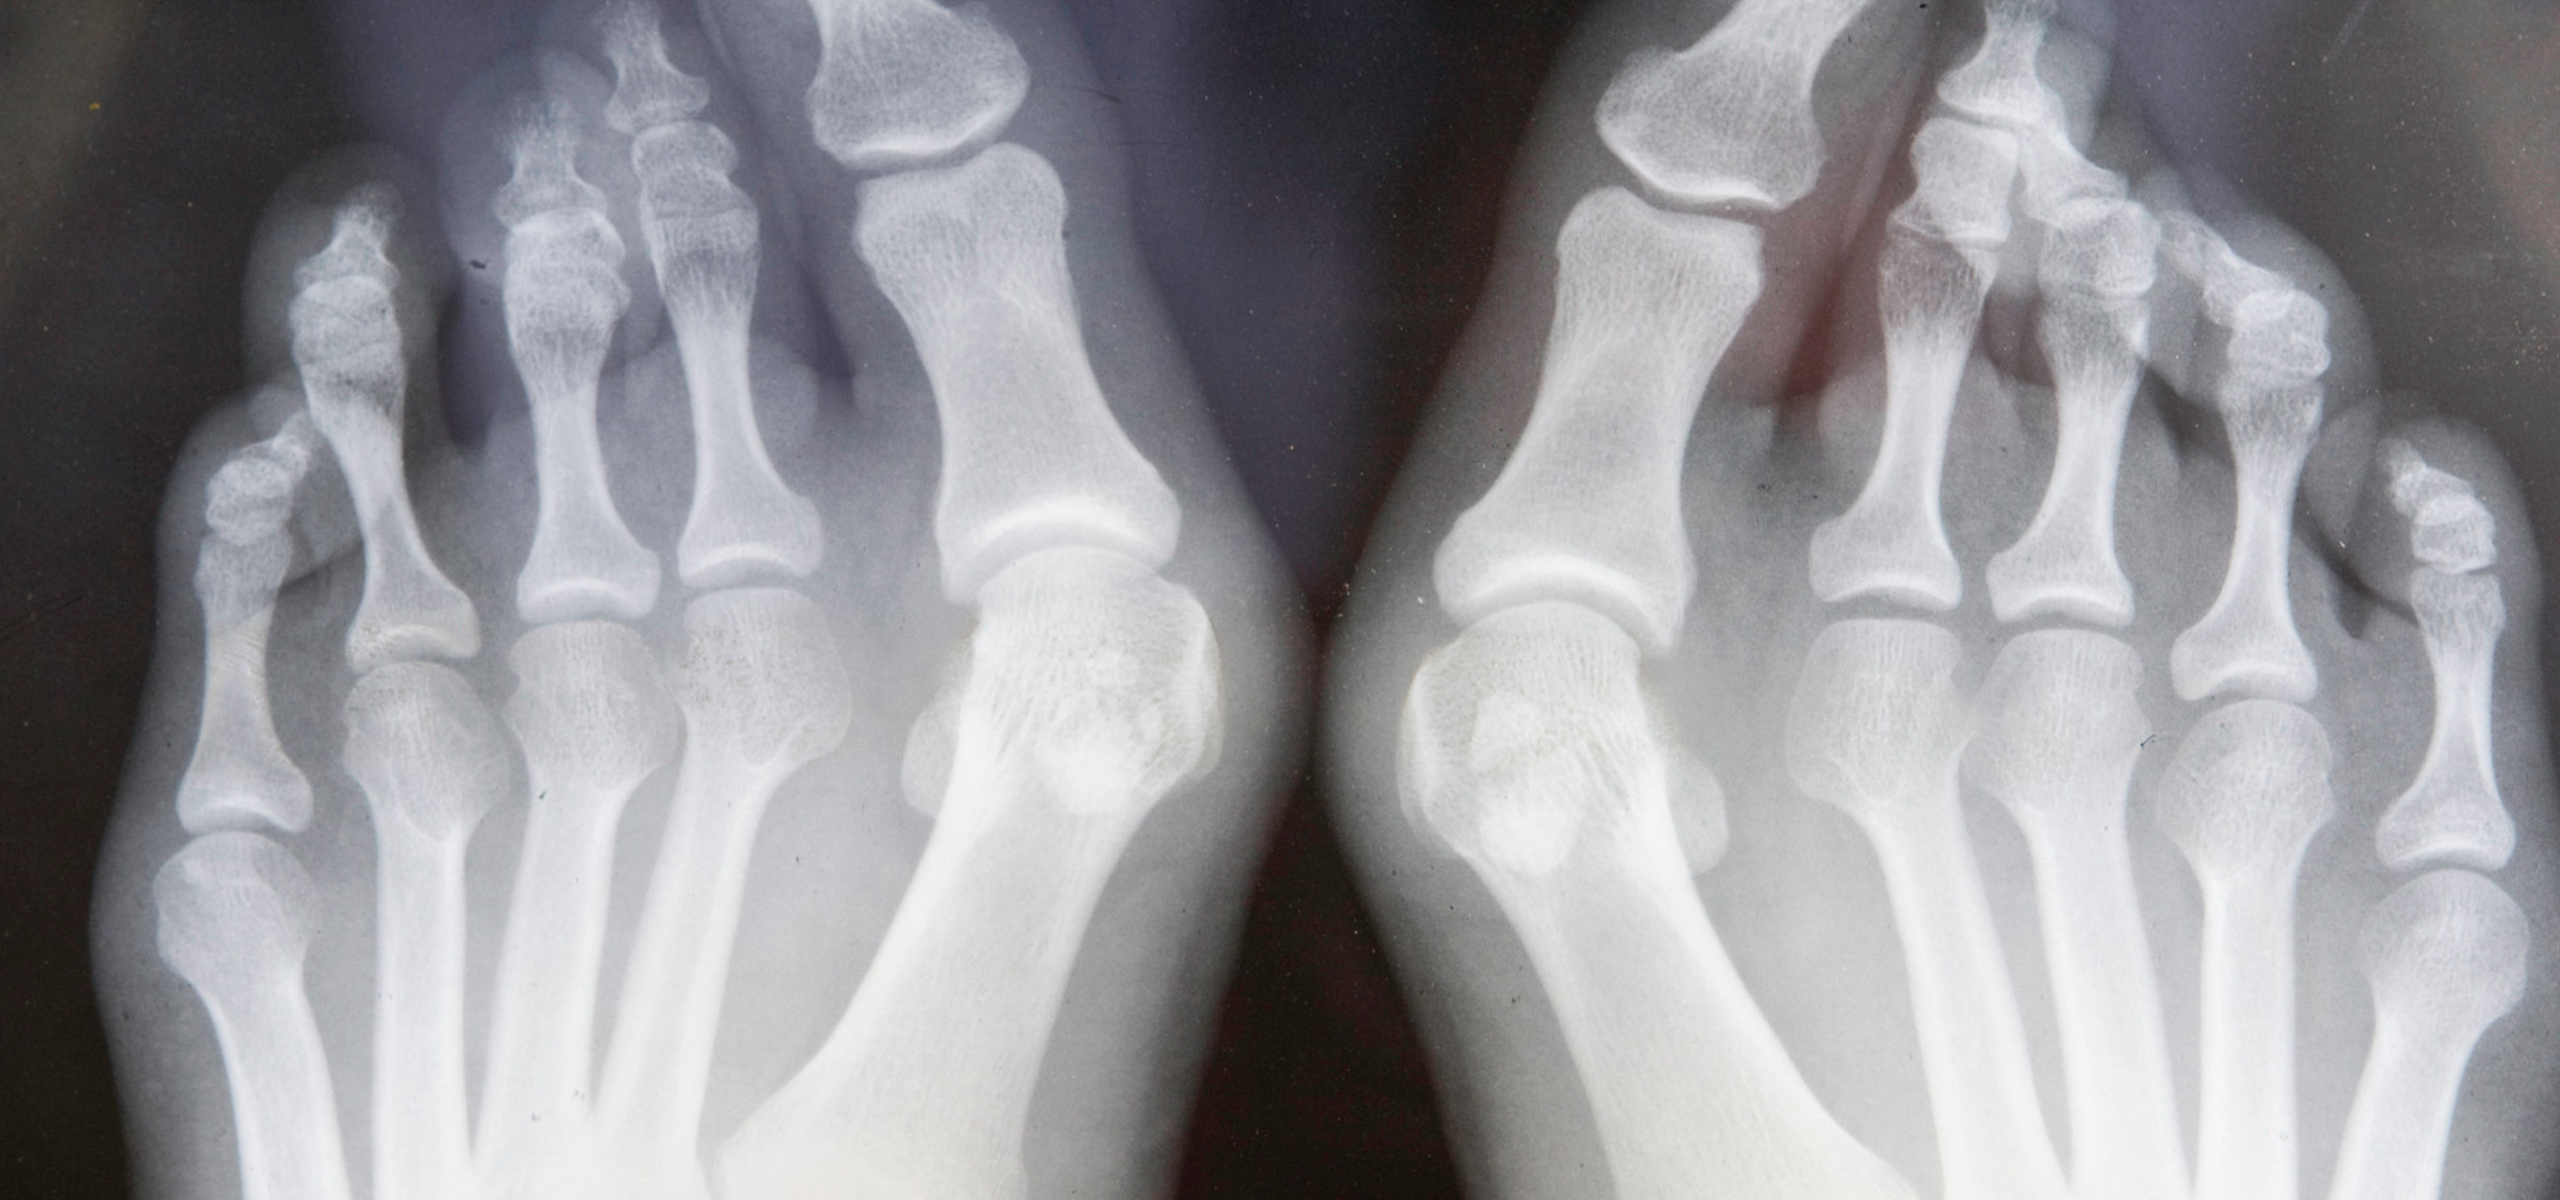

OSTEO-ARTHRITIS

Osteo-Arthritis is a degenerative disorder that causes wear and tear of the joints by damaging the cartilage as a result the bones begin to grind against each other causing pain and swelling that can lead to toe deformities. It is advisable for patients suffering from osteo-arthritis to maintain their feet, by consulting a Registered Podiatrist regularly. Insoles and orthotics are beneficial as they compensate for poor foot function.